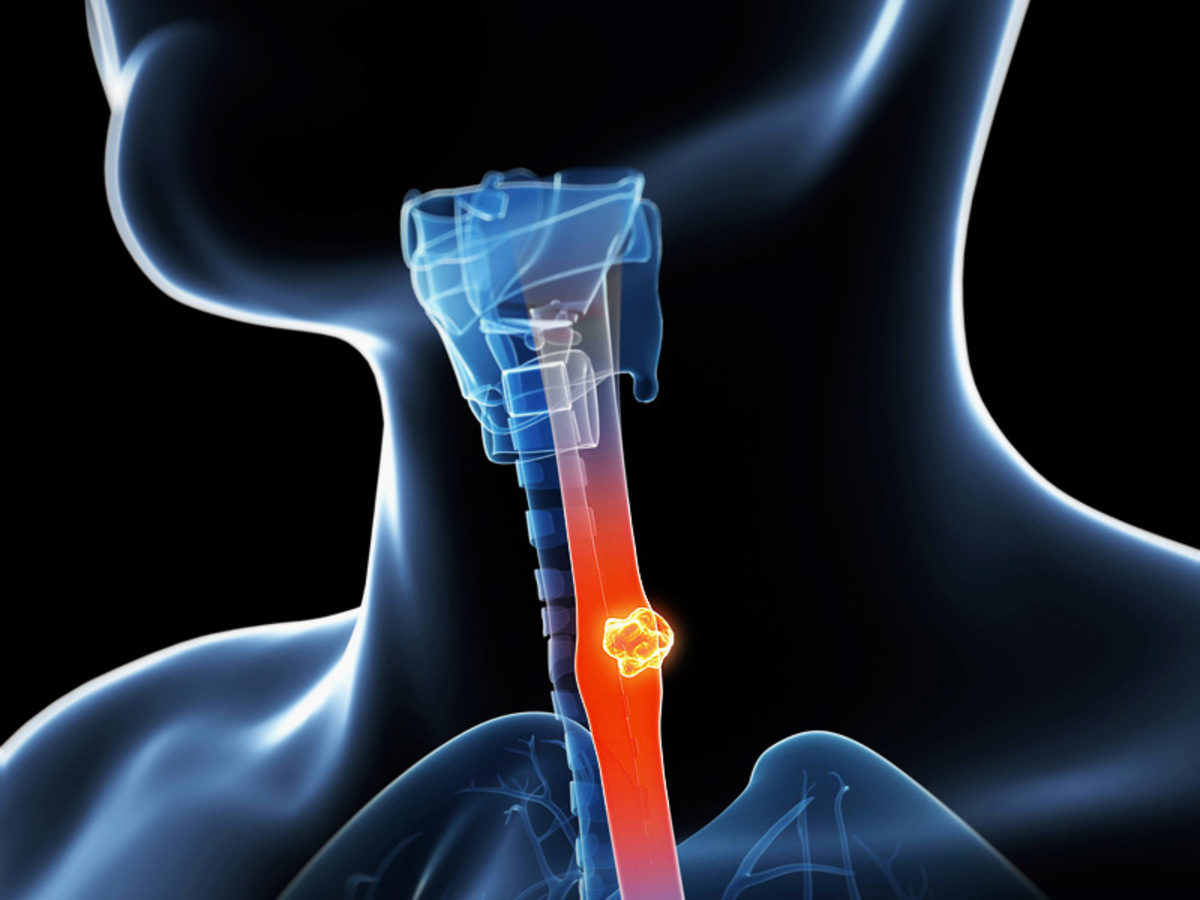

Καρκίνος: Το 40% ΟΛΩΝ των τύπων συνδέεται με τα περιττά κιλά και την παχυσαρκία [vids]

Μια νέα έκθεση προειδοποιεί για το ρόλο της παχυσαρκίας στον καρκίνο. Το 40% όλων των καρκίνων σχετίζεται με την παχυσαρκία, σύμφωνα με τη νέα έρευνα, γεγονός που υποδηλώνει ότι αυτοί οι καρκίνοι θα μπορούσαν να αποφευχθούν αν το βάρος του ατόμου διατηρηθεί υπό έλεγχο.